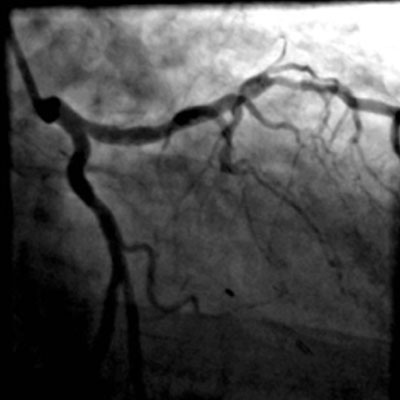

L’échographie intravasculaire aide à déterminer la pathologie sur le site ambigu pour optimiser la stratégie de traitement et l’utilisation du dispositif.

Dans la sténose ostiale, l’échographie intravasculaire aide à déterminer l’emplacement de l’ostium pour diminuer le risque d’échec géographique ou de présence d’entretoises du stent dans l’ostium.